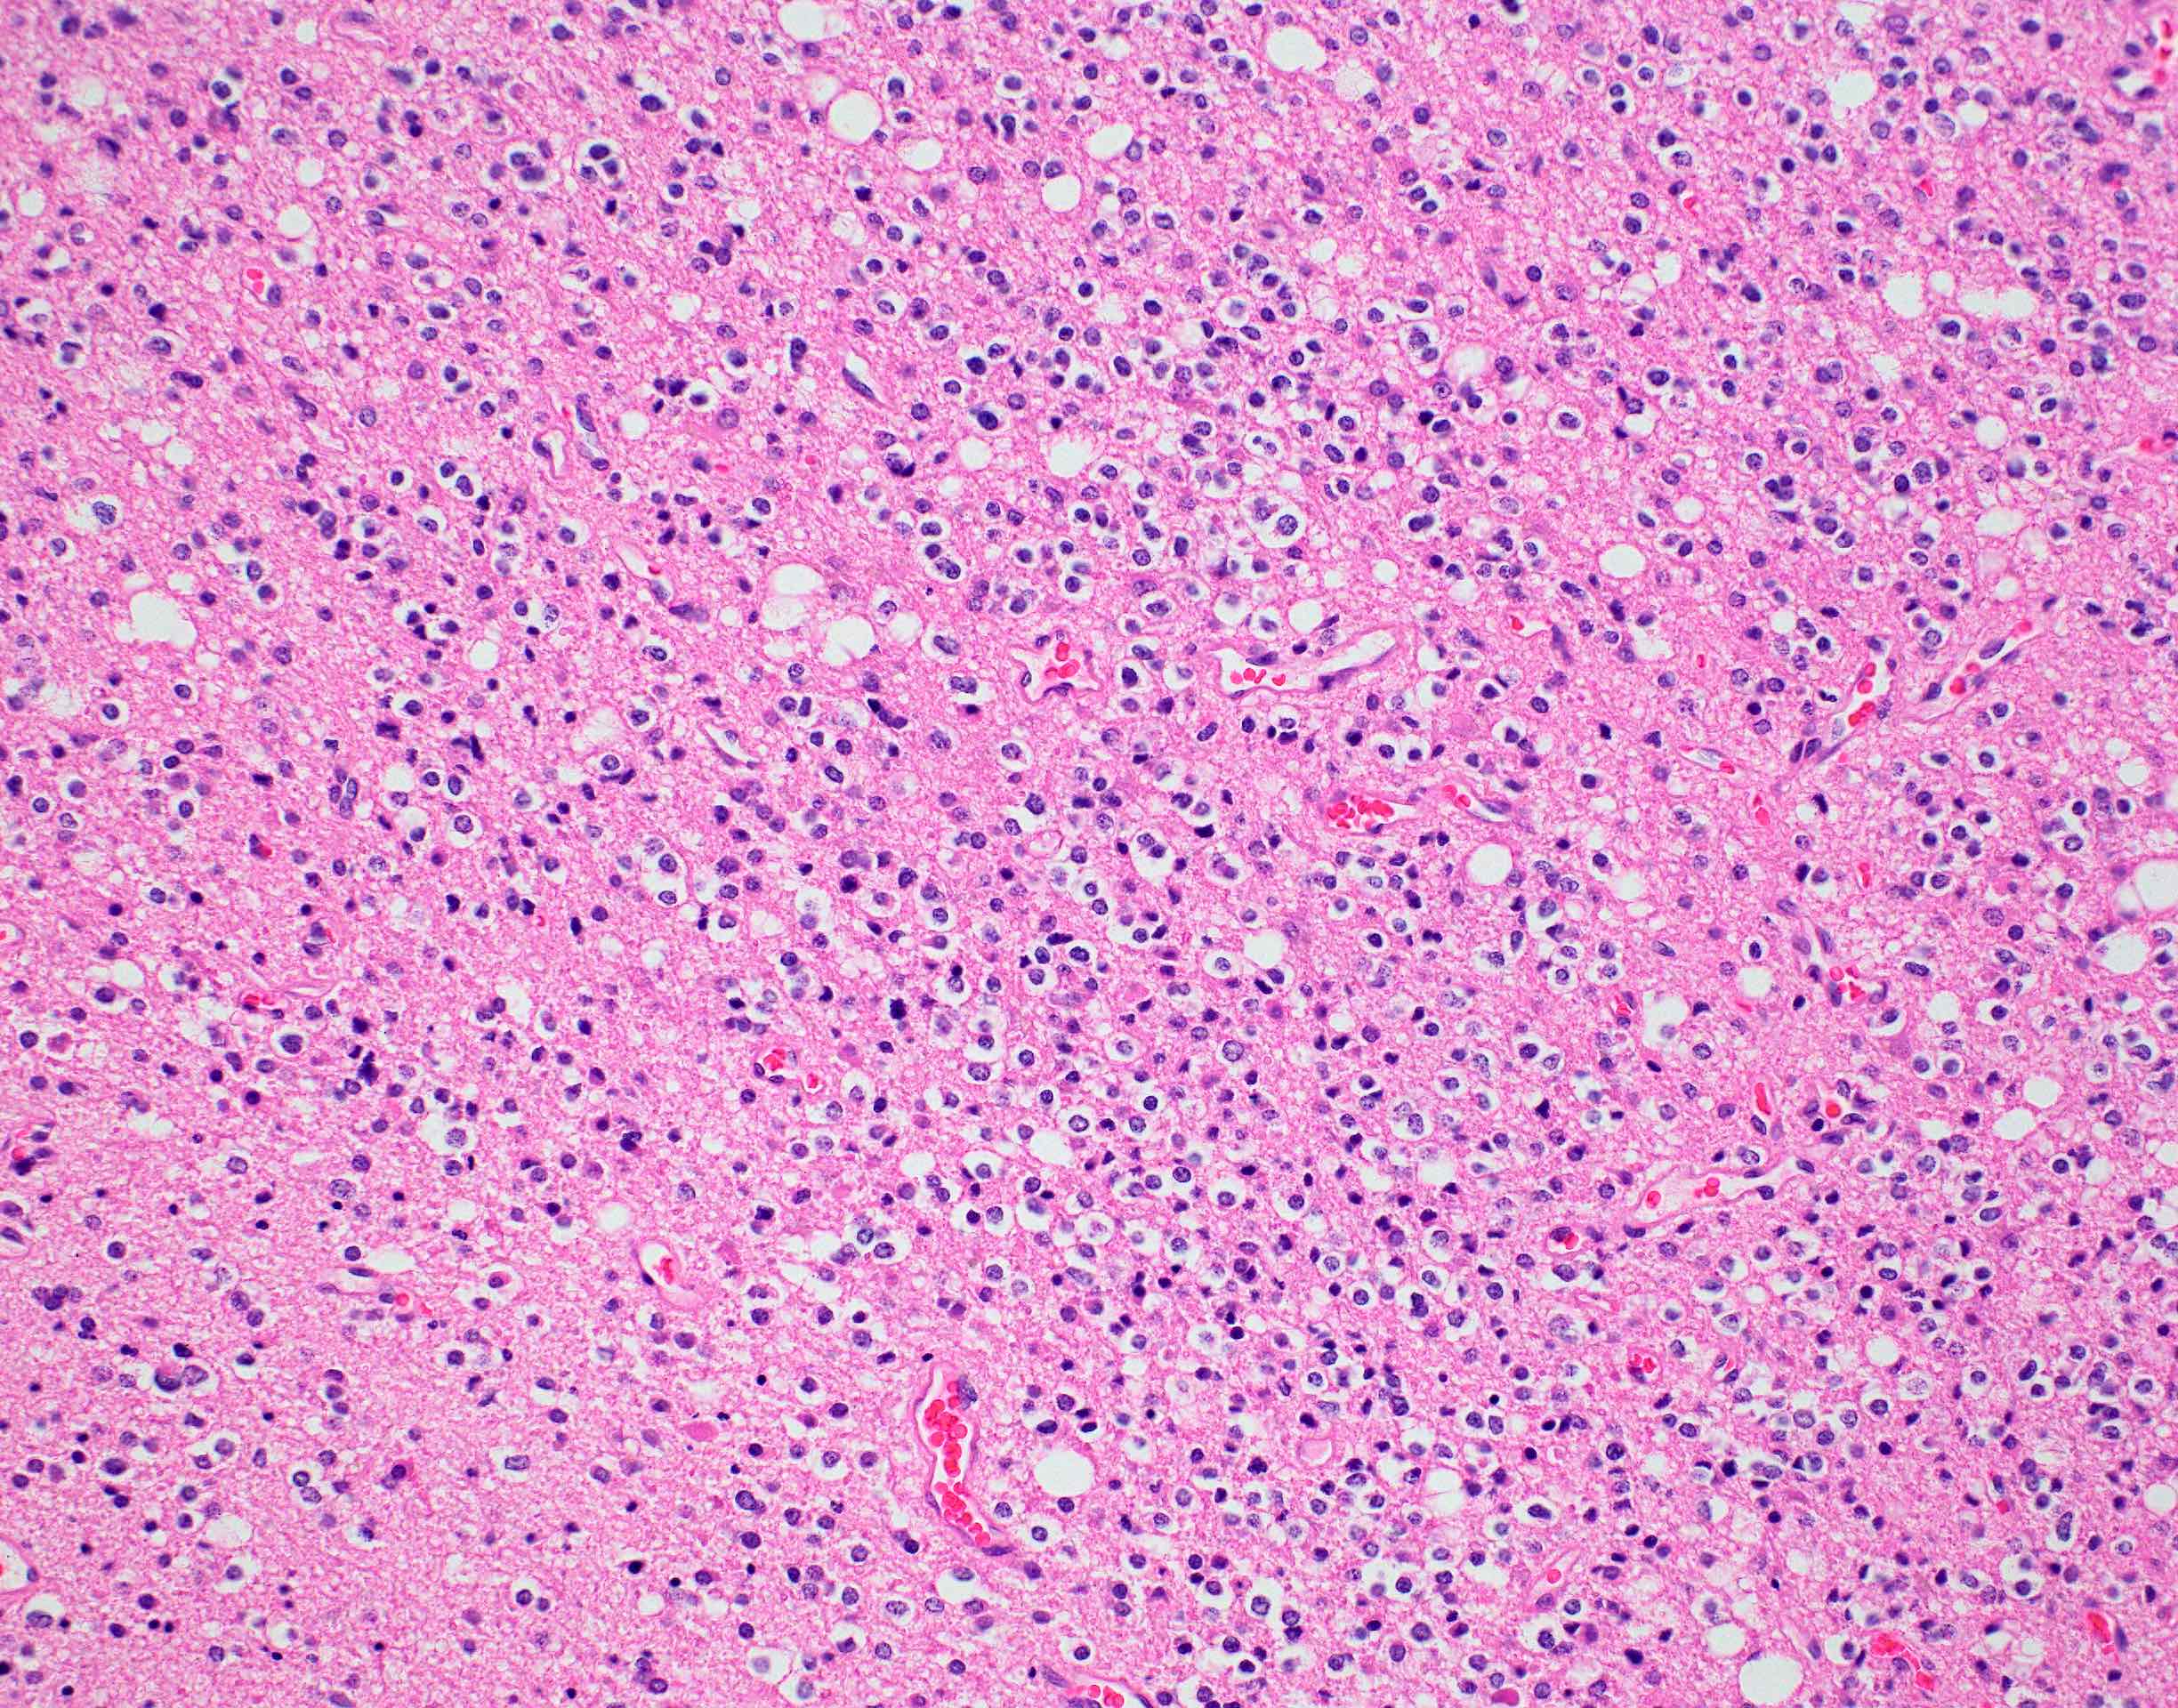

Microscopic (histologic) description

- Closely packed cells with small, round, monotonous nuclei (slightly larger than a normal oligodendrocyte)

- Perinuclear clearing (fried egg appearance)

- Formalin fixation artifact

- Will not be seen on frozen sections or smear preparations

- Network of thin walled, branching blood vessels (chicken wire vasculature)

- Microcalcifications (calcospherites) are characteristic

- Presence of perineural, perivascular or subpial aggregates of tumor cells (secondary structures of Scherer)

- Occasional mitoses and moderate nuclear atypia are still consistent with grade 2 designation (J Neuropathol Exp Neurol 2001;60:248)

- Not uncommon to find well differentiated / fibrillary astrocytic morphology (Acta Neuropathol 1984;64:265)

- Features of CNS WHO grade 3 oligodendroglioma:

- Presence of microvascular proliferation

- Presence of necrosis

- Presence of brisk mitotic activity

- Strict mitotic figure cutoffs do not currently exist; some authors suggest ≥ 6 mitoses per 10 high power fields for WHO grade 3 designation in tumors without necrosis or vascular proliferation (Neuro Oncol 2014;16:1244, Neuro Oncol 2016;18:888)

Microscopic (histologic) images

Contributed by Jared T. Ahrendsen, M.D., Ph.D. and John DeWitt, M.D., Ph.D.